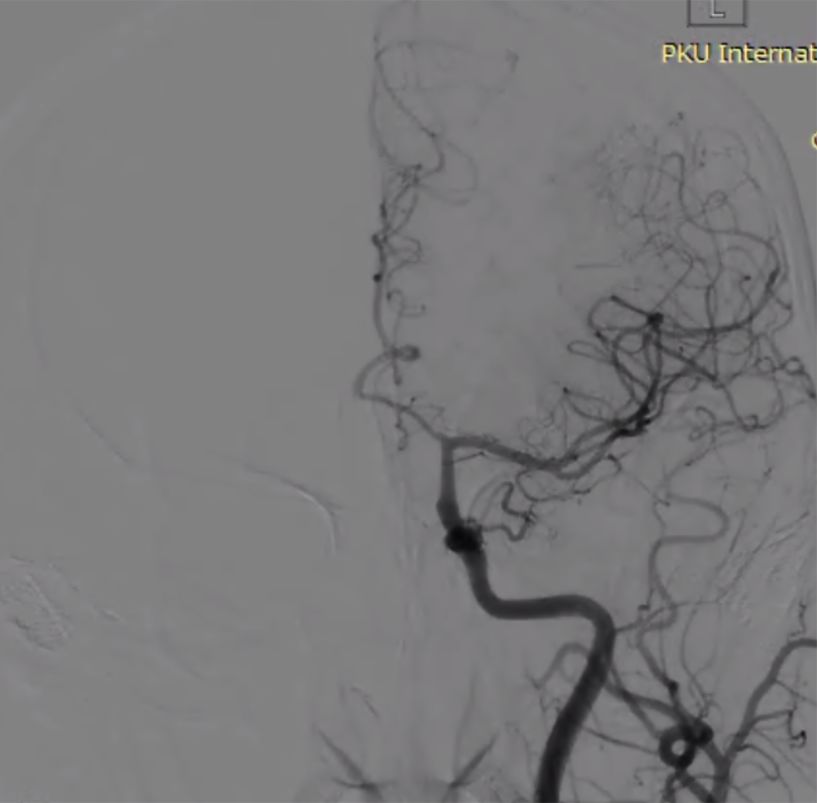

(7)支架重建后正侧位(图10)。

图10

术后复查影像(图11)。

图11